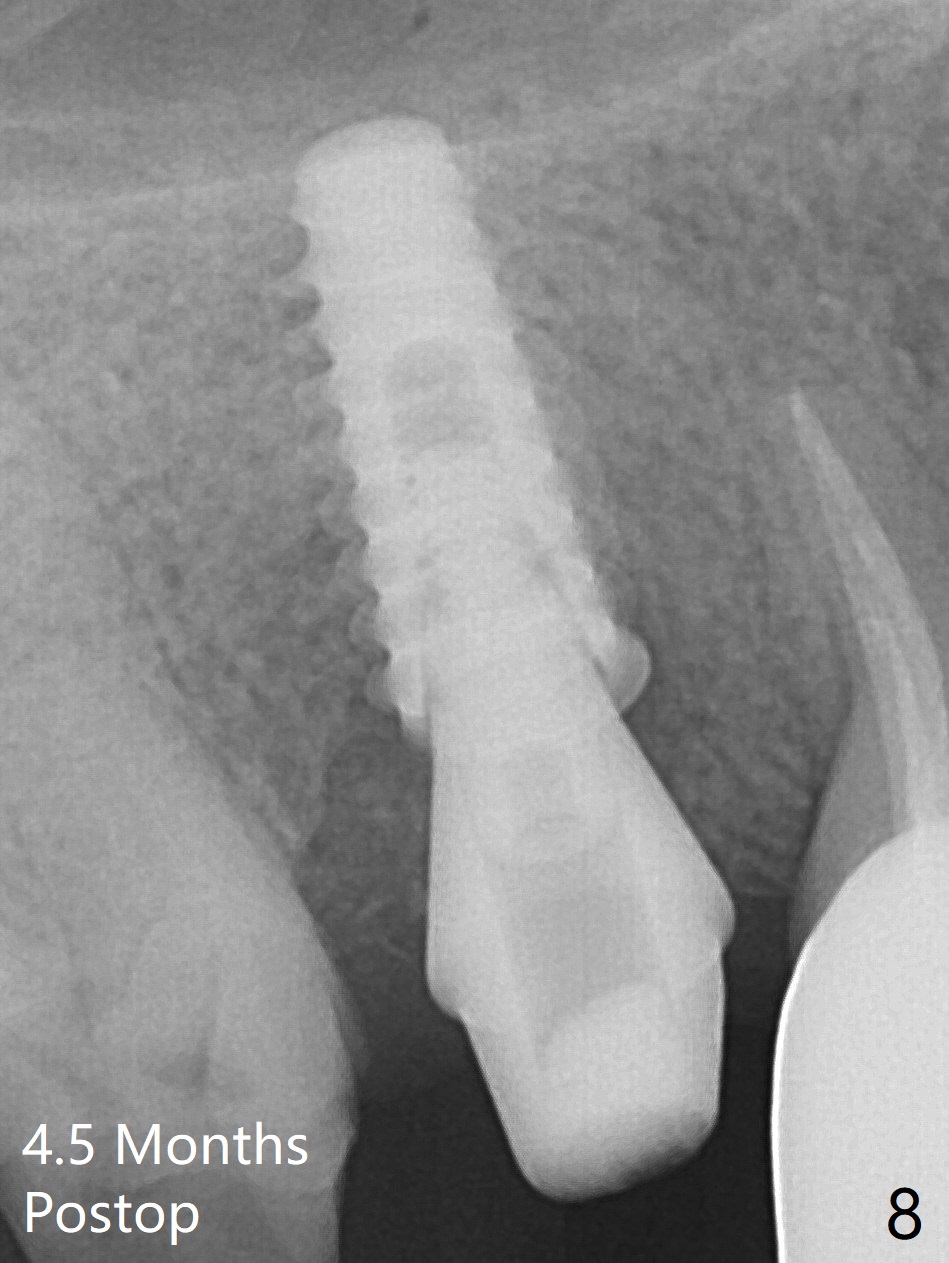

When the tooth #4 with vertical root fracture is extracted, the socket is large, approximately 6x10x10 mm (Fig.1 (mesiodistal x buccopalatal width x depth)). Osteotomy is established in the middle of the socket with 2 mm initial drill for 7 mm, 2.8 and 3.6 mm rounds drills (from DIO Sinus Master Kit) for < 7 mm, and 3.0 and 3.8 mm Magic Expanders. A 4x11 mm dummy implant is placed with insertion torque of 30 Ncm (Fig.2,3 (^: sinus floor)). There is a gap between the socket wall and the implant (*). To reduce the gap and periimplantitis, a 5x11 mm IBS implant is placed with insertion torque > 50 Ncm after further osteotomy using Magic Drills (Fig.4,5). Following placement of 5.5x4(4) mm abutment (A) and bone graft (data not shown), a splinted provisional is fabricated at #3 and 4. The provisional is stable 3 months postop (Fig.6,7). The peri-implant gaps (Fig.4,5) seem to disappear (Fig.6) with the help of bone graft. Bone graft appears to remain between the implant fins (Fig.7 arrows). Impression is taken 4.5 months postop (Fig.8,9). The abutment dislodges 4 months post cementation. After retightening, there is clearance for shim after use of 2 layers of thick articulating paper. Is the abutment screw too short? Or Titanium V is too hard for welding? The abutment/crown dislodges again 1 year 3 month post cementation; it appears that the fact that the implant is placed deep contributes to abutment screw loosening (Fig.10,11). An abutment screw will be buried inside the implant well 10 days post initial retightening.